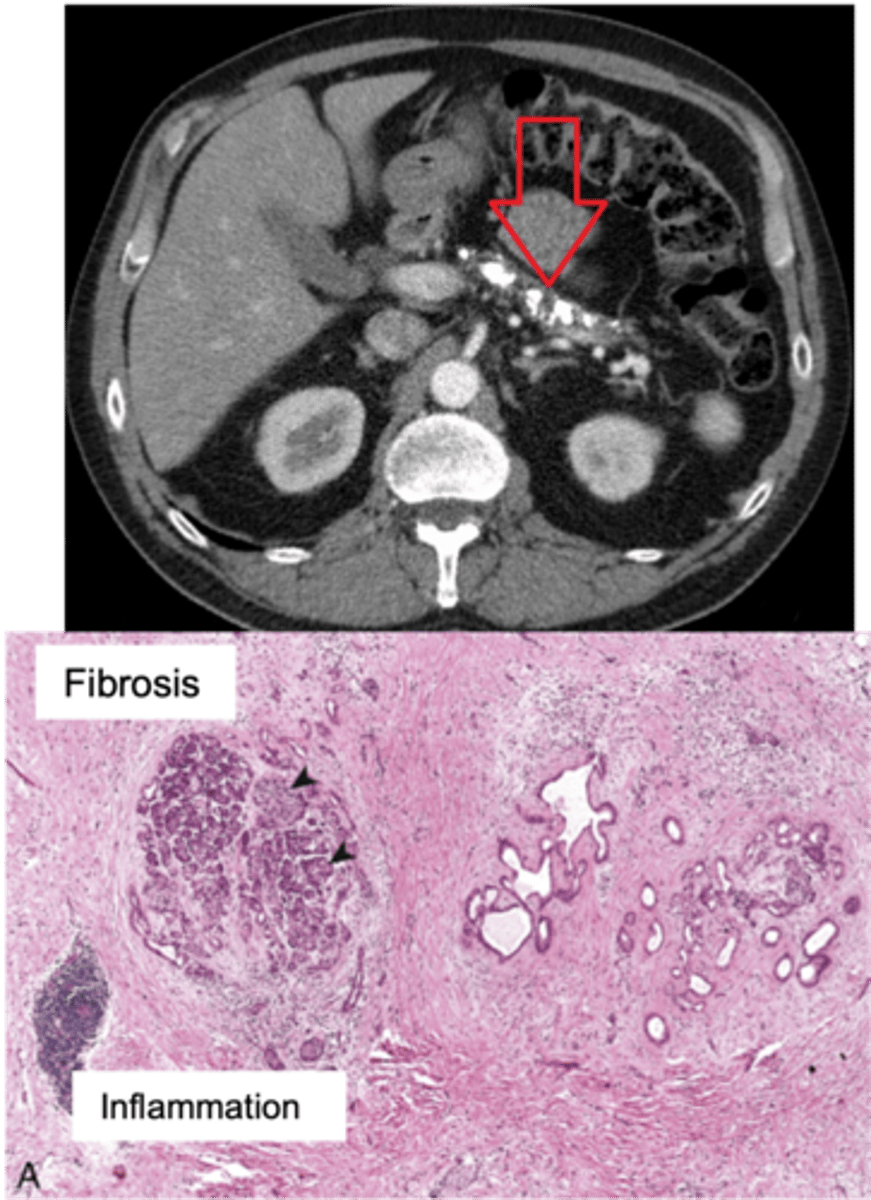

Chronic Pancreatitis

Define Condition:

Prolonged pancreatic inflammation --> Irreversible destruction of exocrine pancreas + Fibrosis

-Hx:

> MCC = Chronic Excess EtOH use

> May be Idiopathic

> 25% have GENETIC PREDISPOSITION = Cystic Fibrosis, SPINK1 (encodes trypsin inhibitor) mutation

> Repeated episodes of Acute Pancreatitis

> More in MALES

-Path: Chronic Pancreatic Injury --> Inflammatory Mediators (TGF-Beta & PDGF) ==> Activation/Proliferation of Pancreatic Stellate Cells --> More Periacinar Myofibroblasts ==> Collagen Deposition & Fibrosis

-Sx/PE:

> Chronic/recurrent Abd Pain

> Steatorrhea & Malabsorption

>> Pancreatic Burnout of enzymes (Pancreatic Insufficiency) --> Less Proteases/Lipases --> Can't Absorb Fat ==> Fat Soluble Vitamin Deficiencies

-Dx:

> Imaging (CT): Multiple pancreatic calcifications

> Gross:

>> FIRM w/ dilated ducts

>> Calcified concretions

> Biopsy:

>> Parenchymal fibrosis

>> Smaller size/number of acini --> Acinar Loss

>> Variable dilation of ducts +/- Inspissated concretions

>> Chronic Inflammation

>> Eventual loss of islet of langerhans

-Tx:

-Prog:

> Secondary D2M (loss of Islet of Langerhans)

> Pancreatic Insuffiency

> Pancreatic Pseudocysts

> Increased risk of Pancreatic Carcinoma